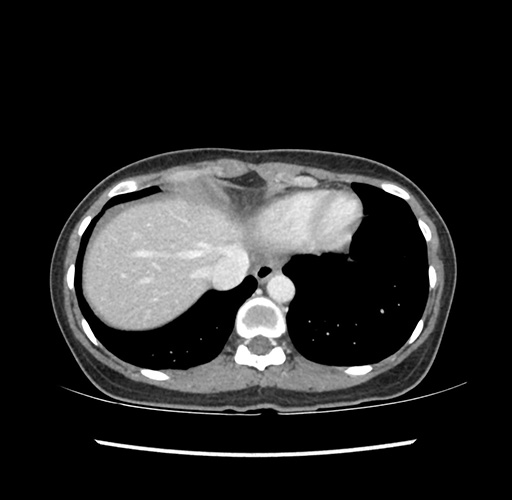

Imaging Analysis

Look through the patient's CT scan to identify any areas of concern for the necessary procedure.

Based on your CT findings, which issue(s) would give reason for "planned slowing down moment(s)" in this case?